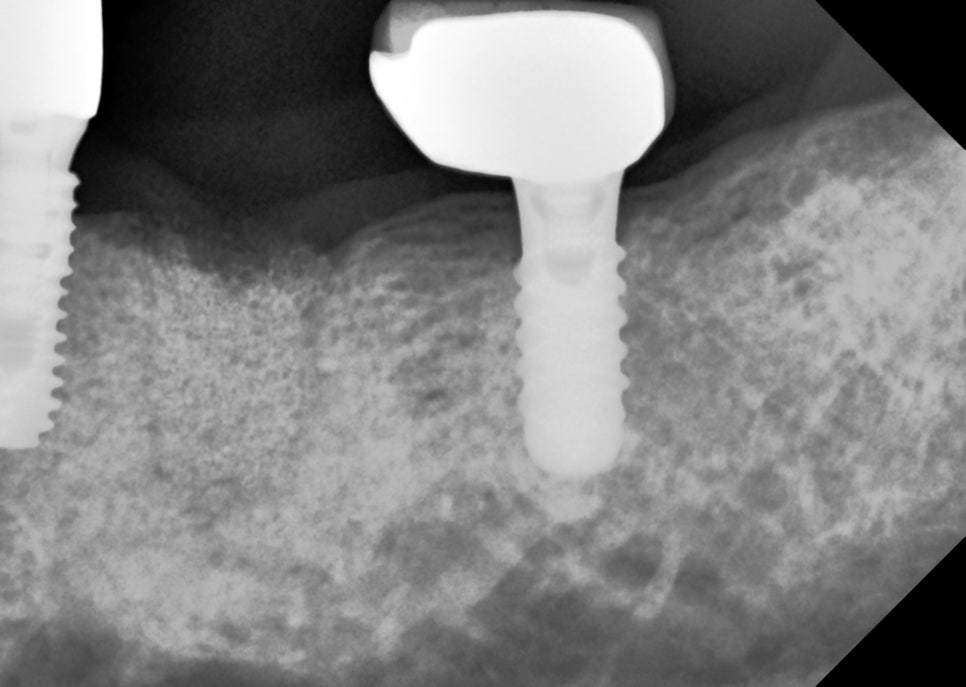

뼈이식과 지연 식립

잇몸뼈를 다시 건강하게

뼈이식은 부족한 잇몸을

보강하는 치료 방법이에요.

치아를 뽑은 자리나

잇몸뼈가 얇아진 부분에

인공 뼈나 자신의 뼈를 이식해서

건강한 뼈가 다시 자랄 수 있는

환경을 만들어줍니다.

그래서 발치 후 뼈이식을 해두면

다음에 수술할 때

더 안정적인 결과를 기대할 수 있어요.

그림2. (그림1)에서 임플란트 발치 후 뼈이식